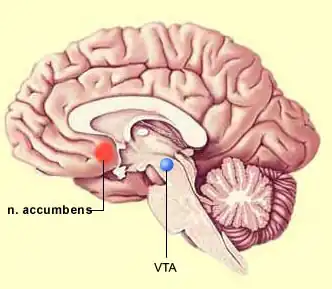

Images from neurological research can create images that show regions in the brain accociated with feelings of sadness. Research can not state the exact cause for emotions, rather areas within the brain activated when emotions arise. There is still debate between the amount of genetic factors and environmental influences which contribute to activating these areas of the brain. It is unexceptional to experience emotion such as sadness, as it is part of human physiology. Hormones play a vital part in emotions. Some primary hormones are, Cortisol, a hormone related to stress, with contributes to poor intellectual functioning, negative affect and low health. Testosterone has a high contribution to sex and arousal, Oxytocin is a hormone which leads people to seek comfort in times of need, bonding tendencies to cope with issues in the world. Dealing with negative feelings requires a release in dopamine. Dopamine enhances functioning. Neuroimaging and neurological studies have found that sad facial expressions enhanced activity in the left amygdala and right temporal pole. Sad expressions activate the amygdala region and lesions’ in this region have demonstrated difficulty in recognising expressions. Emotional expression is learnt through the amygdala (Dolan,1999). Dopamine originator of Norepinephrine,which has resulted from tyrosine which comes from diet, comes from regions in the brain stem, the locus ceruleuis and lateral tegmentum. These regions send axons to the cerbellum, spinal cored and amygdala. This shapes conciousness and emotional response. A shortage in dopamine production can effect norepinephrine production. This results in lethargy and low levels of energy, which results in a struggle to get up and go. An excessive amount of dopamine can lead the psychotic moods (Mendius, 2008). Positron emission tomography (PET) studies of emotion have reflected that areas of the brain which have shown activity for sadness are bilateral inferior and orbitofrontal cortex. bilaterally in anterior cingulate,medial prefrontal, and mesial temporal cortex, as well as in brainstem, thalamus, and caudate/putamen (Lane et al,1997). Ekman and Friesen focussed on facial expressions and the human race being universal and without influence from cultural factors. Studies in this field find that infants exhibit expressions of anger, fear, happiness, sadness, surprise and disgust even in such beginning life (Lane et al,1997). Similar to Ekman and Friesens study with men and facial expression, Lane, Reiman, Ahern, Schwartz,& Davidson (1997), experimented on the brain activity and emotions. Using 12 neurologically and psychiatrically, between 18and 30 who were female participants Positron emission tomography was used to measure regional brain activity. There were 12 conditions for each participant, happiness, sadness, and disgust and three control conditions, each induced by film and recall. Emotion and control tasks were alternated throughout. Condition order was pseudorandomized and counterbalanced between the particpants. For each emotion and control condition the brain regions were examined. Results support that varying brain regions are responsible for various emotion.